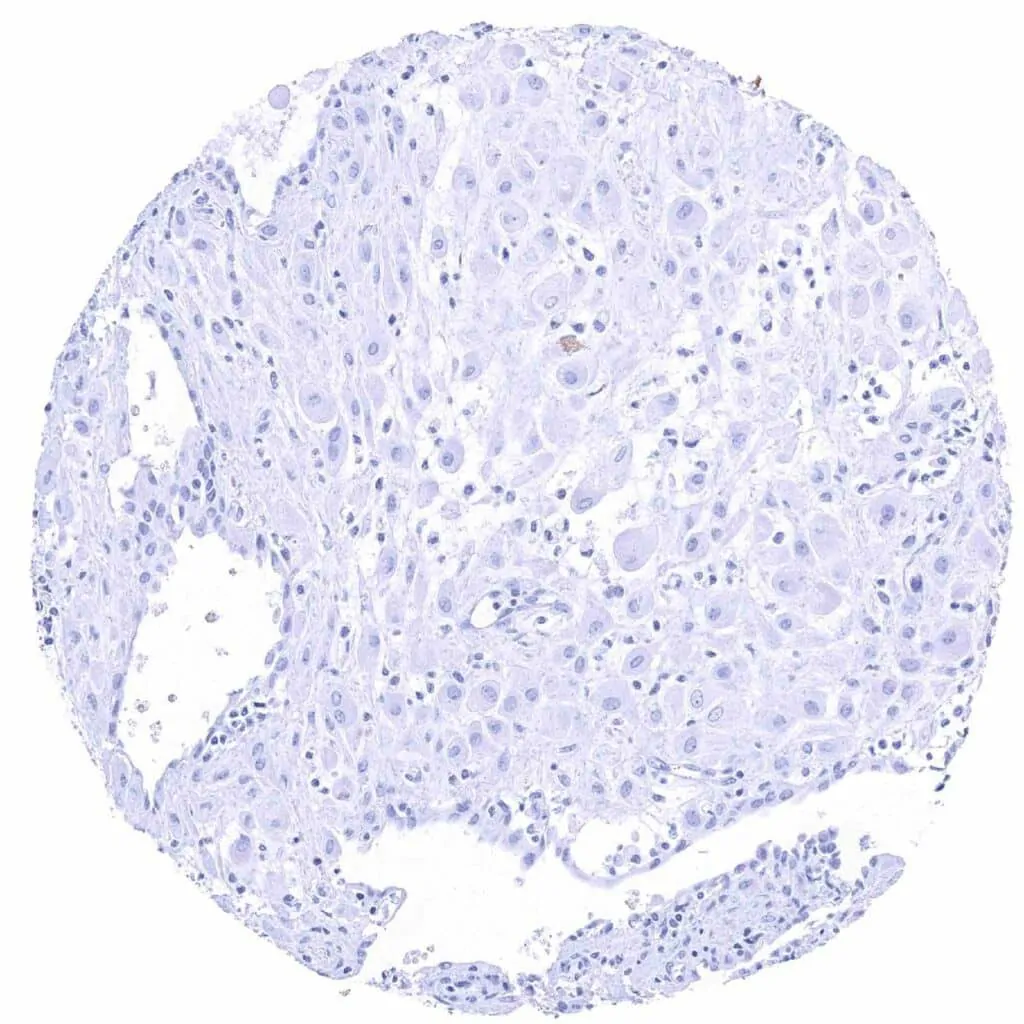

Tonsil, surface epithelium

Tonsil